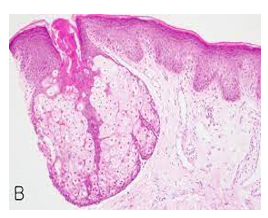

Upon microscopic examination, mature sebaceous glands appear aggregated subjacent to mucosal epithelium. The visible sebaceous glands appear in continuum with superimposed cutaneous surface and are devoid of associated hair follicles [6,7]. Nevertheless, a ductal communication with superficial epidermis may be absent [6,7].

The morphological countenance is akin to normal cutaneous adnexal sebaceous glands. Superimposed stratified squamous epithelium demonstrates parakeratosis and exhibits subjacent lobules of mature sebaceous glands [6,7].

Figure 7: Fordyce's granules depicting an enlarged, lobulated sebaceous gland with a superimposed hyperkeratotic stratified squamous epithelium (15).